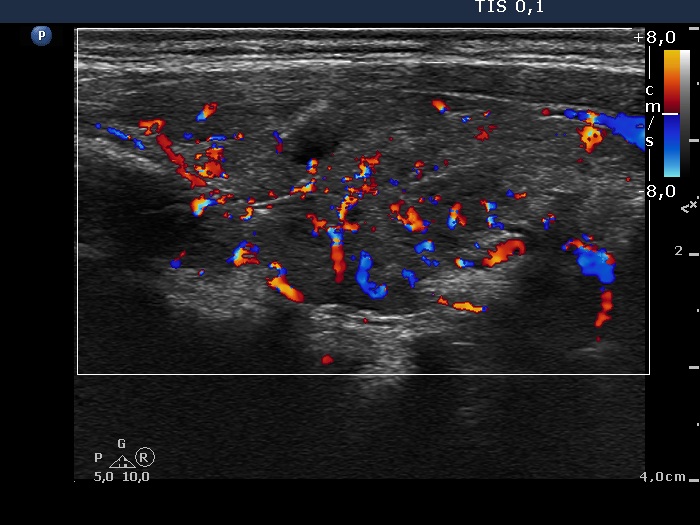

Discrete lesion or nodule in Hashimoto's thyroiditis - case 9 (644) (ultrasonographic picture 4)

Right lobe, longitudinal scan, color Doppler mode. The intrathyroidal vascularization is increased while the lesion is avascular.